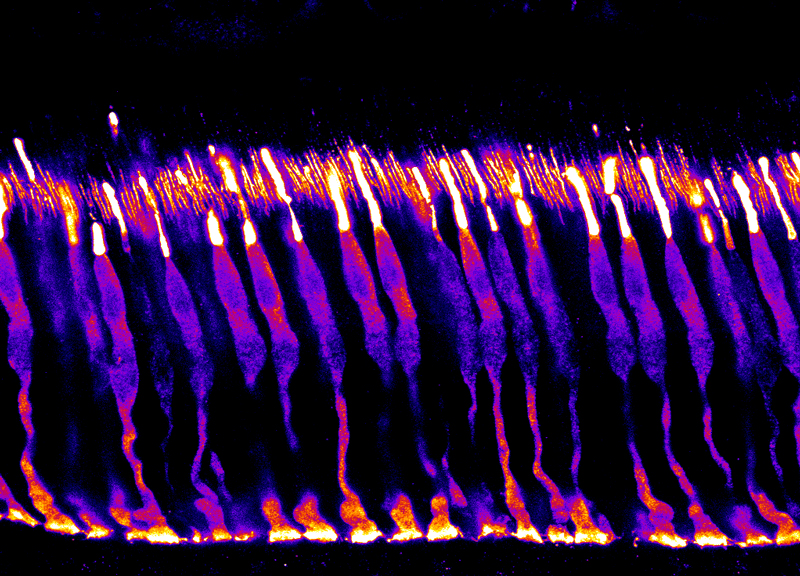

Maya-Vetencourt, J. F. et al. A fully organic retinal prosthesis restores vision in a rat model of degenerative blindness. Nat. Mater. 16 681-689 (2017).

Ghezzi, D. et al. A polymer optoelectronic interface restores light sensitivity in blind rat retinas. Nat. Photonics 7, 400–406 (2013).

Dr Serge Picaud, PhD is Research Director (INSERM, orcid.org/0000-0002-0548- 5145). He is the head of the Department of Visual Information processing at the Vision Institute. His team is investigating visual function in normal and pathological conditions to understand our vision, develop models of retinal pathology and propose new therapeutic treatments. In the last 10 years, the team has been involved in developing strategies for restoring vision from retinal implants to optogenetic therapies. These strategies are first examined on in vitro models such as retinal explants from rodent, primate or even post-mortem human retina and then validated on living rodents or non-human primates. These validations involve functional in vitro measurements from patch-clamp, multielectrode array (MEA) recording or calcium imaging and in vivo measurement like MEA recording as well as ultrafast ultrasound imaging providing greater resolution than MRI. The team has also access to phenotyping platforms on both rodents and non-human primates including the following technologies (eye fundus examination, Scanning laser ophthalmoscope (SLO), Optical coherence tomography (OCT), electroretinogram and visual evoked potential recording). Finally, restoration of vision is demonstrated by behavioural evaluations such as saccades in non-human primates. These preclinical studies have enabled the team to contribute to several products entering into clinical trials like retinal prostheses with Pixium Vision (NCT03333954) and optogenetic therapy with Gensight biologics (NCT03326336).

Busskamp V, Duebel J, Balya D, Fradot M, Viney TJ, Siegert S, Groner AC, Cabuy E, Forster V, Seeliger M, Biel M, Humphries P, Paques M, Mohand-Said S, Trono D, Deisseroth K, Sahel JA, Picaud S, Roska B. Genetic Reactivation of Cone Photoreceptors Restores Visual Responses in Retinitis pigmentosa. Science (2010) 329: 413-7.